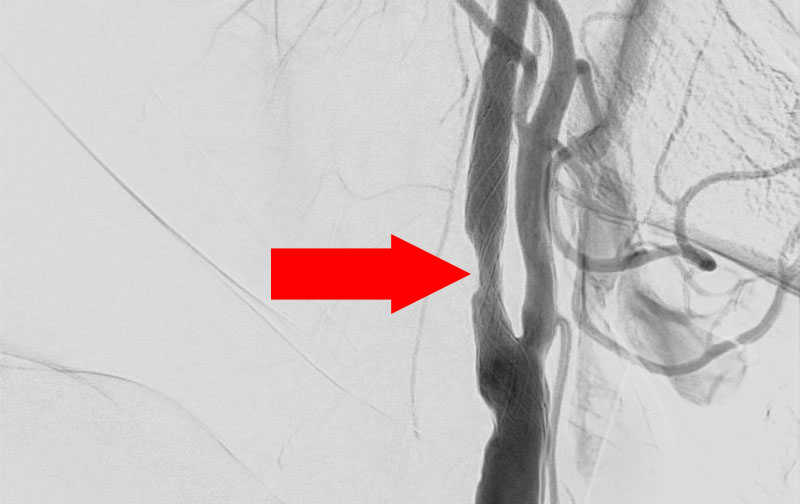

'21年12月

右頚部内頚動脈狭窄症

70代

大阪府の病院

No.1163 手術前

No.1163 手術中

No.1163 手術後